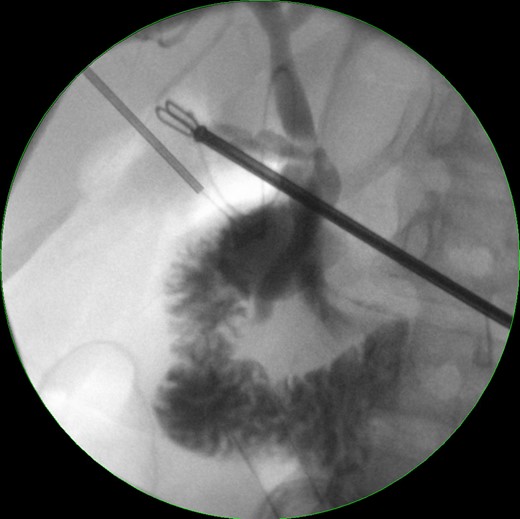

A 39-year-old healthy female, presented to our emergency department due to abdominal pain, nausea and vomiting. She was febrile, with a tender right hypochondrial and epigastric region. Her laboratory results showed a normal complete blood count and C-reactive protein level. Liver function test showed an elevation in total bilirubin at: 42 mmol/L, direct bilirubin level at: 29 mmol/L, gamma-glutamyl transferase (GGT) level at :160 U/L and Lipase level at: 34 000 U/L. An abdominal US showed two separate gallbladders with a sludge (Fig. 1). Abdominal CT scan showed a Balthazar grade C pancreatitis and confirmed the presence of a double gallbladder (Fig. 2). An MRCP confirmed the double gallbladder (Fig. 3). An ERCP was performed with evacuation of biliary debris in the common bile duct (CBD). The patient was discharged home after appropriate medical treatment a couple of days later with a full normal liver function test. Two months later, a laparoscopic cholecystectomy was performed where the two gallbladders were dissected with a dome-down technique, from the gallbladder fundus towards the neck (Fig. 4), the cystic duct and artery were identified. An intraoperative cholangiography was performed which showed patent intrahepatic ducts, cystic and CBD (Fig. 5). A Hem-o-lock® clip (WECK Closure System; Teleflex Inc., Morrisville, NC, USA) was then placed on the main cystic duct (Fig. 6), and another Hem-o-lock® clip was placed on the cystic artery. Figure 7 showing the gross specimen. The final histopathology report concluded two separate gallbladders, each having its own cystic duct, with both cystic ducts joining to form a main cystic duct.

Laparoscopic view showing two separate cystic ducts joining to form one main cystic duct, with a clip on it.